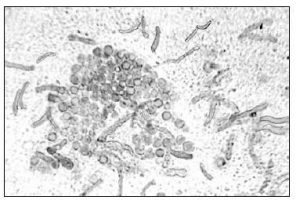

Treatment of skin scrapings, nails, or hairs with potassium hydroxide (KOH) dissolves tissue material, leaving the alkali-resistant fungi intact. Microscopic examination of KOH preparation reveals the presence of fungal structure and aids in diagnosing mycoses.

KOH is a strong alkali. When specimen such as skin, hair, nails or sputum is mixed with 10% w/v KOH*,* it softens, digests and clears the tissues (e.g., keratin present in skins) surrounding the fungi so that the hyphae and conidia (spores) of fungi can be seen under a microscope.

The KOH test is one of the main methods of diagnosing fungal infections in diagnostic laboratories. It is used as a primary screening tool. This wet-mount procedure helps to visualize fungal elements but may not necessarily identify the species of the fungi.